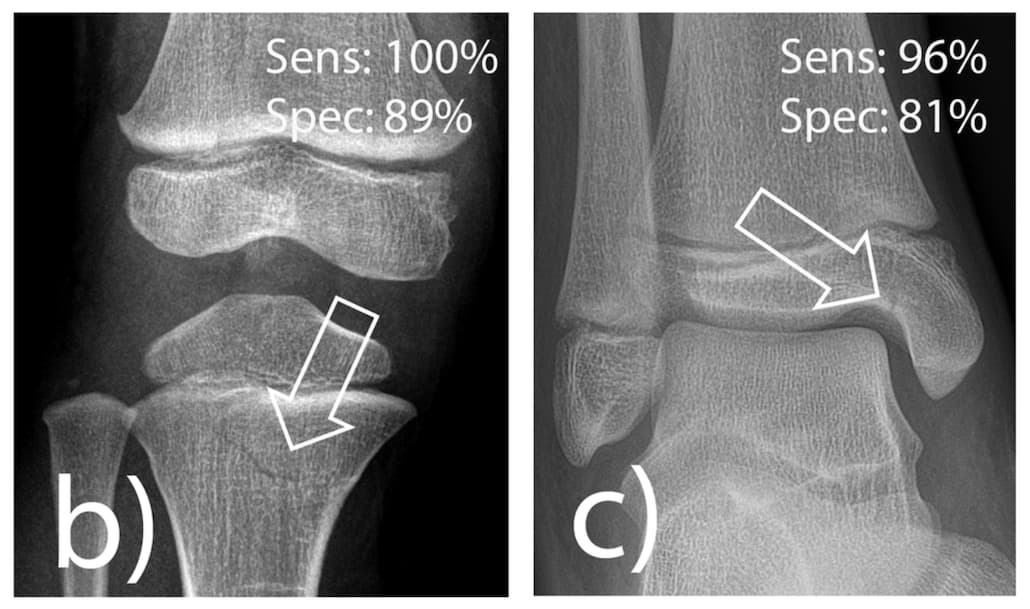

Une IA dédiée pour identifier les fractures en radiologie pédiatrique

En traumatologie pédiatrique, les solutions d’IA ne pas toujours pertinentes pour assister les praticiens qui cherchent à identifier une anomalie musculo-squelettique. Des chercheurs allemands ont publié un article dans la Revue European Radiology dans lequel ils évaluent les performances d’un algor...

Identifier une déchirure radiale oblique du ménisque latéral par IRM

Selon une étude publiée dans l’American Journal of Roentgenology (AJR), l'IRM permet de diagnostiquer avec fiabilité les déchirures radiales obliques du ménisque latéral. Elle montre une sensibilité et une spécificité suffisantes pour identifier ce type de déchirure bio mécaniquement important assoc...

Une IA entraînée sur des cohortes hétérogènes est plus performante pour identifier les fracture en radiographie

Pour améliorer le diagnostic de fracture en radiographie conventionnelle assisté par l’IA, celle-ci doit être entrainée sur des cohortes hétérogènes. Une étude publiée dans la Revue European Radiology évalue un outil d’IA conçu en inde pour l’aide à l’interprétation de patients néerlandais. Les cher...